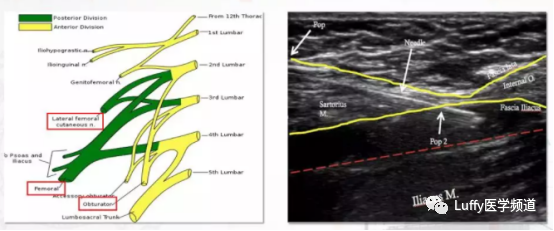

患侧超声引导高位髂筋膜阻滞,予0.25%罗哌卡因35ml

轻比重单侧腰麻(患侧向上),使用0.25%小剂量轻比重罗哌卡因5.5ml(13.75mg),推注30—40 s,患侧向上体位保持10~15 min,然后启动其他操作